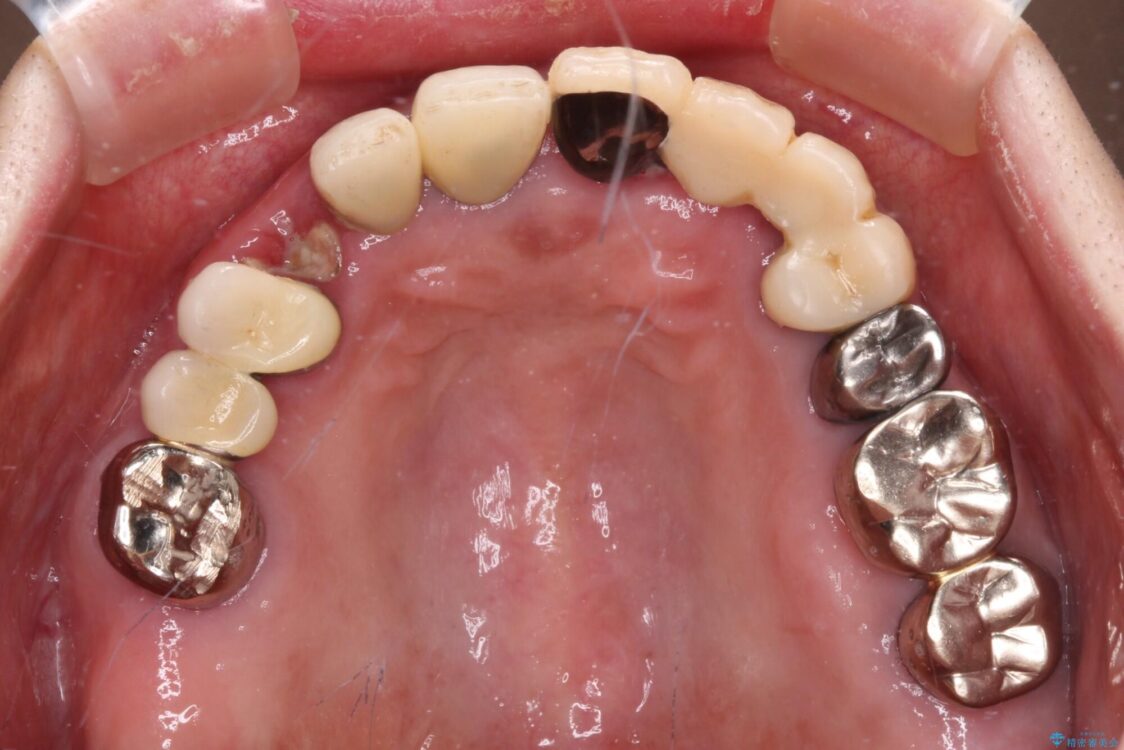

抜歯の必要な前歯や、以前治療した前歯のクラウンの外観を気にして来院された患者様です。

上顎犬歯や下顎大臼歯は、必要なところはインプラントを埋入することとしました。

クラウンが不適合であったり、根管治療の必要なほどの痛みのある歯であったり、見た目の気になる前歯などをオールセラミッククラウンに補綴治療を行うこととしました。

治療前

• 前歯をきれいにしたい インプラントや部分矯正を用いた総合歯科治療 治療前画像